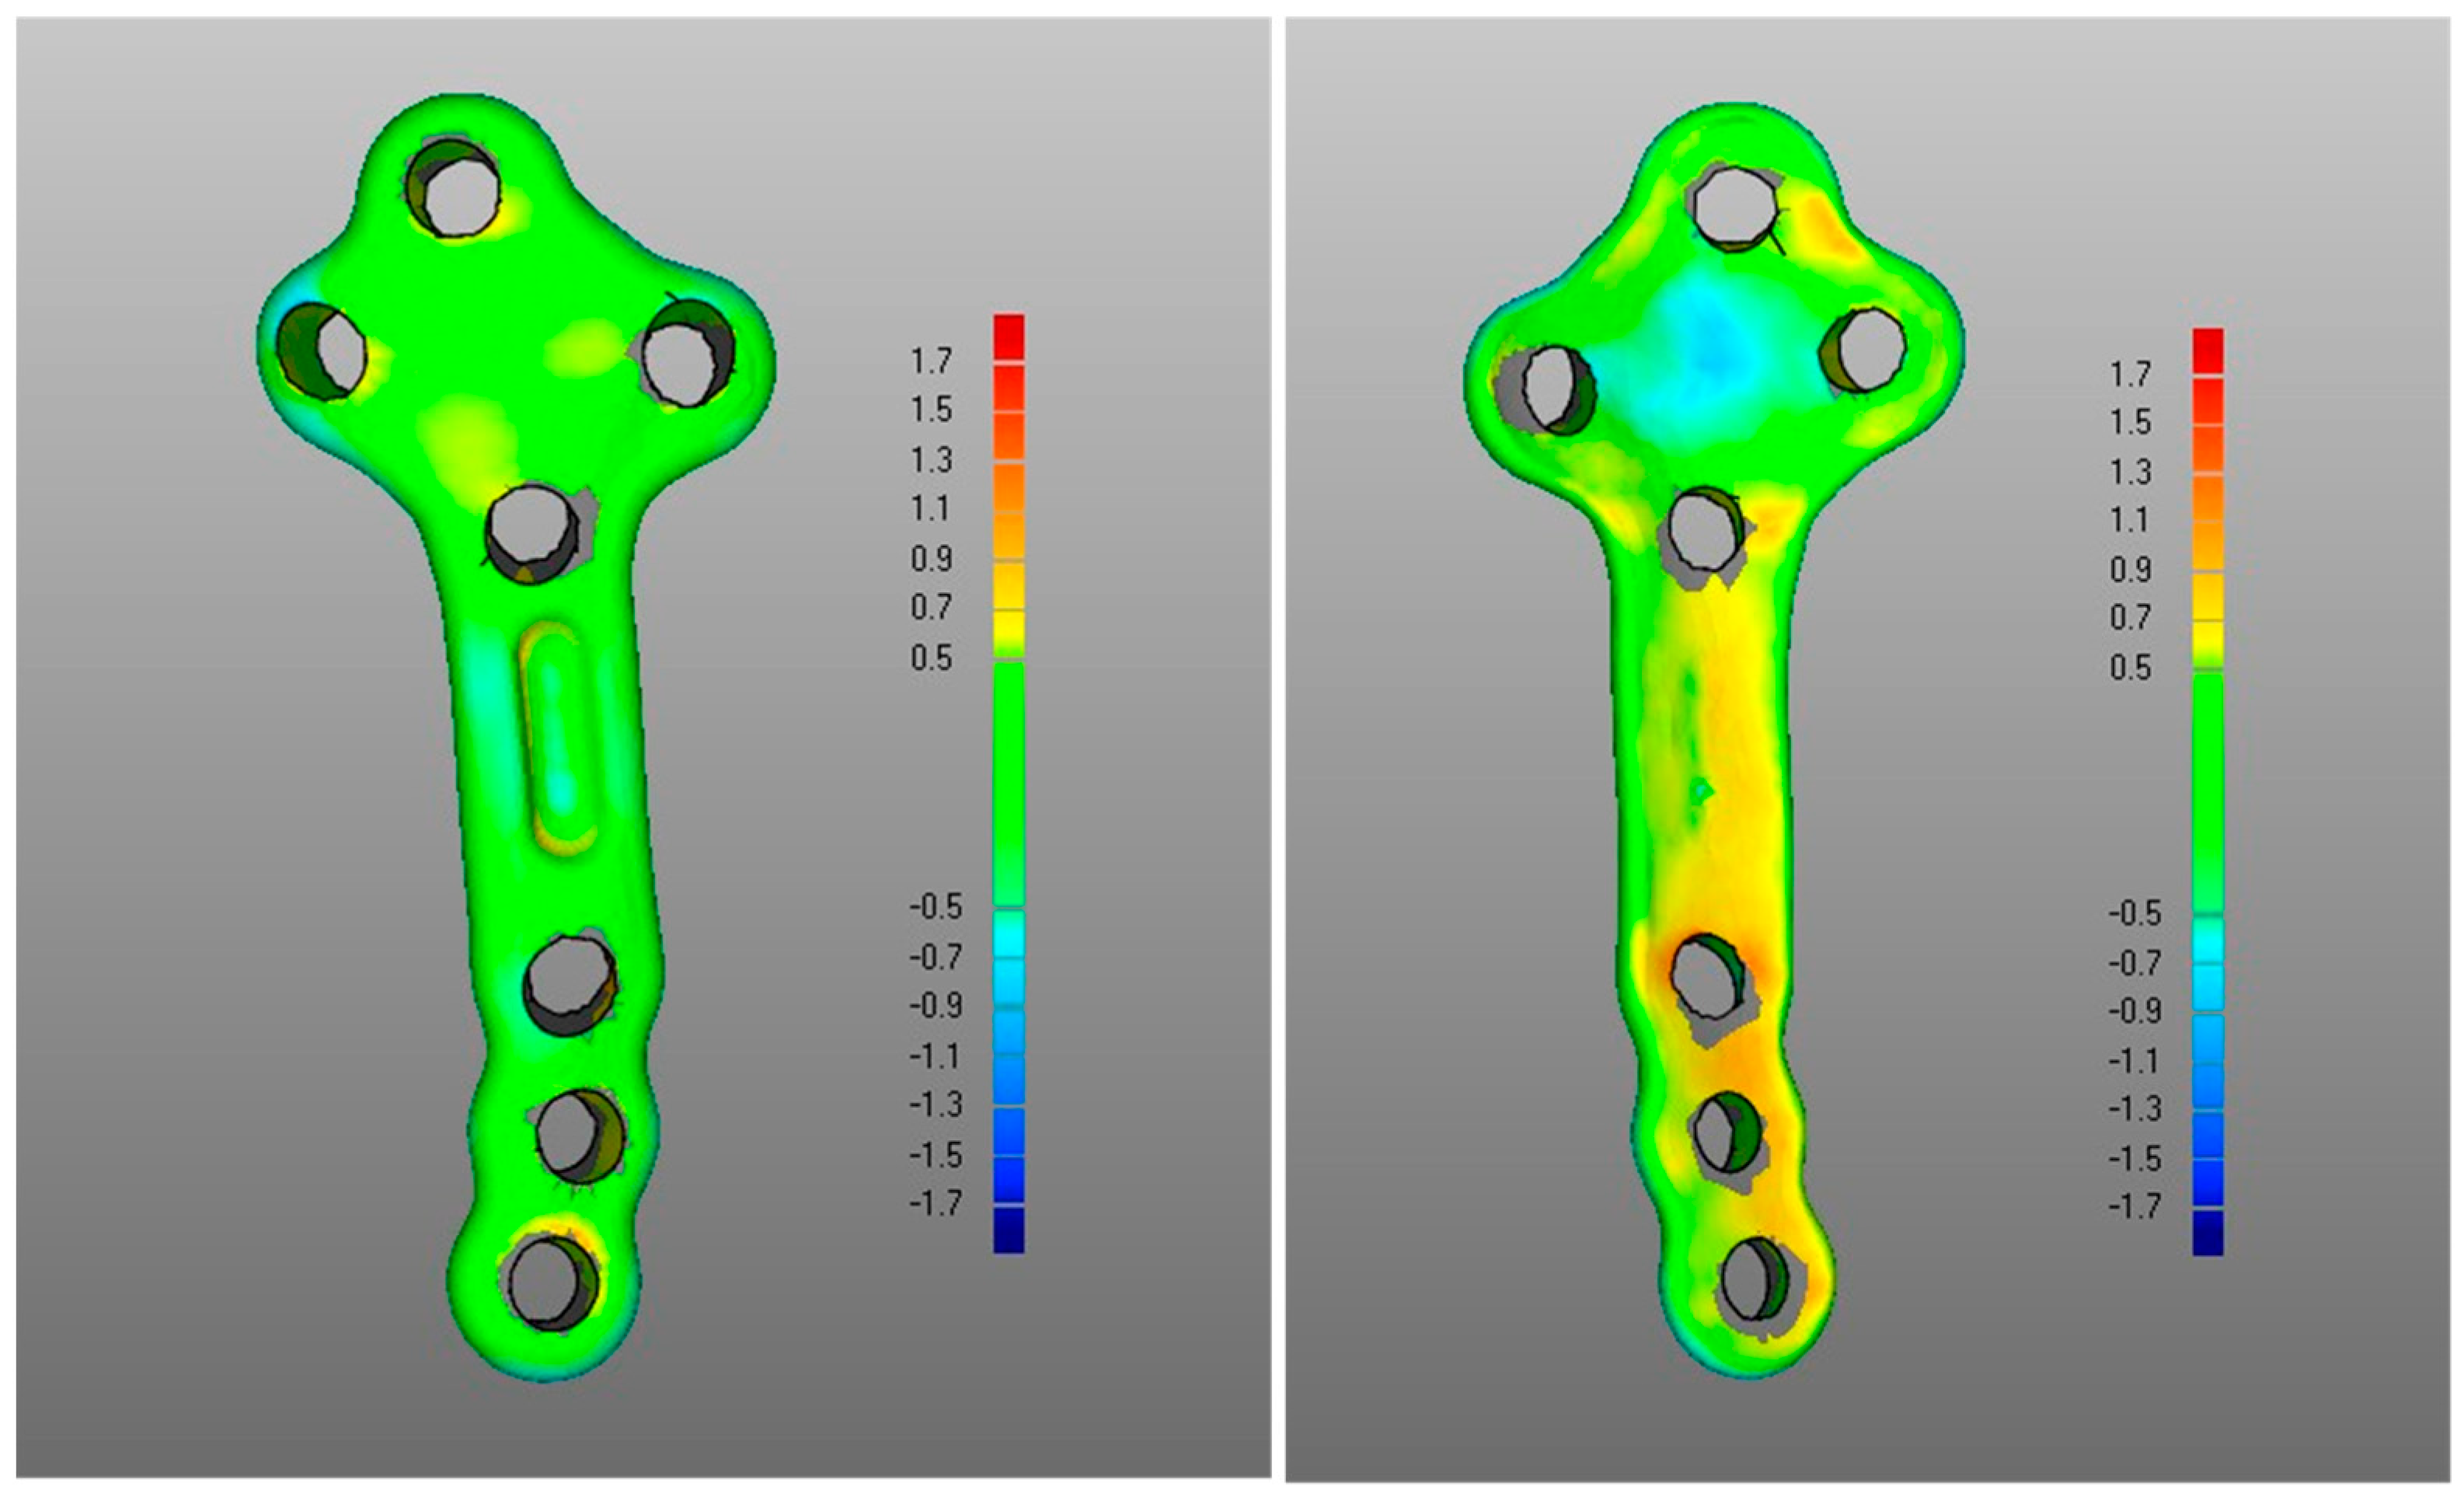

- The DMA values associated with the deformation of the fixation plate (average for was 0.4 mm, was −0.2 mm, with DSD of 0.4 mm) were all less than the critical value, i.e., 1 mm (Table 1) and with most of the points in the safety zone (Table 2), indicating that the overall shape of the metal plate was maintained after surgery at follow-up (Figure 3 and Figure 5).

- Regarding the matching of the plate surface contour to the tibia, the comparison between PLA, i.e., iii-a (Figure 6 left), and POST, i.e., iii-b (Figure 6 right), the low DMA values (Figure 3 and Table 1) reveal a very good replication of the planned contour matching of the plate to the tibia in the POST condition. In iii-a comparison, there was no negative value, i.e., penetration, of the test surface relative to the reference (Table 2).